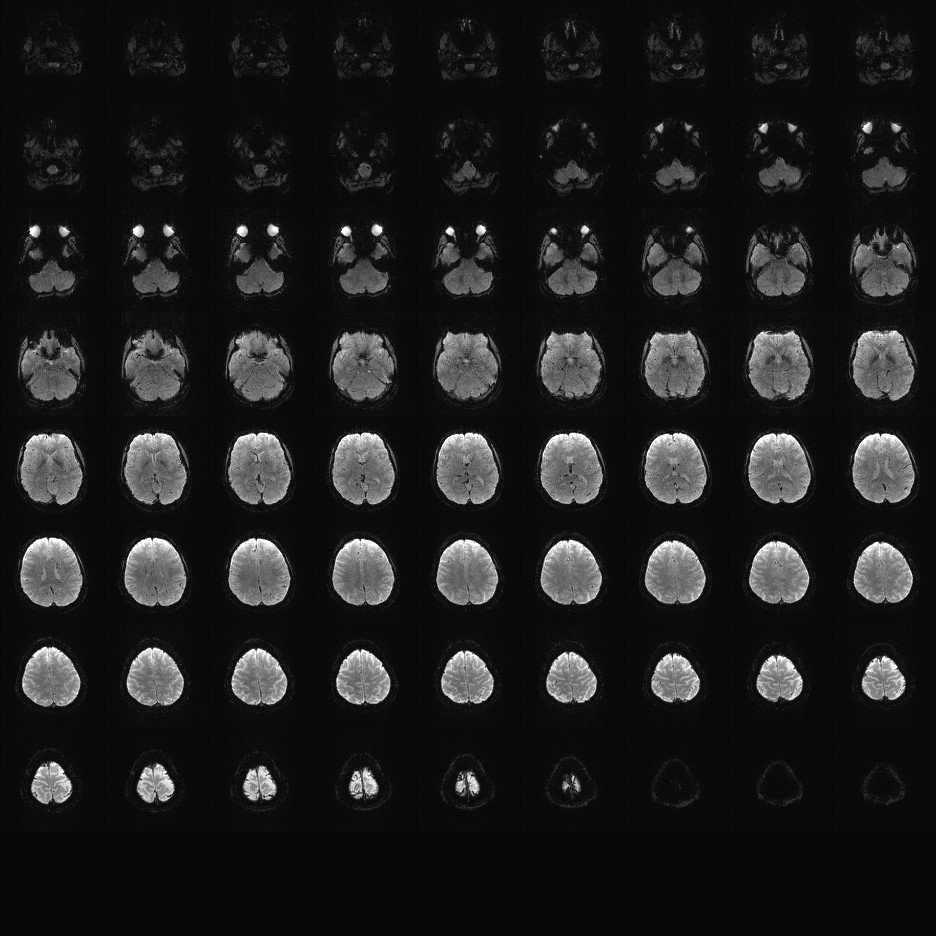

Multi-banded RF pulses can be used to accelerate volume coverage along the slice direction by simultaneously exciting and acquiring multiple slices and subsequently unaliasing them using parallel imaging principles and the spatial information available in multi-channel RF array coils.

This allows for a direct reduction in the volume TR by the number of simultaneously excited slices (i.e., the multiband (MB) factor or the slice acceleration factor).